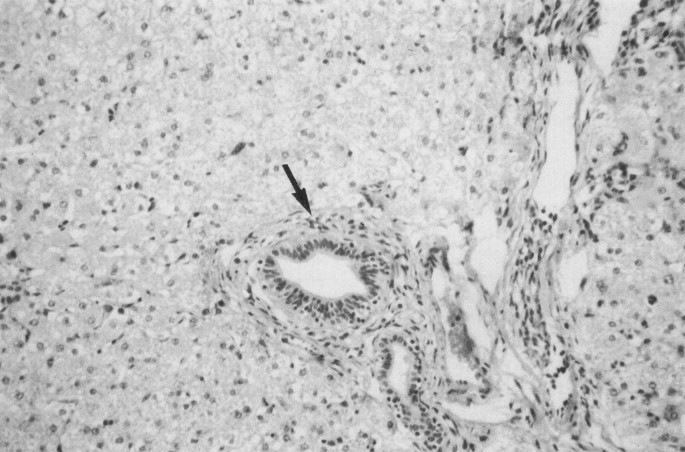

The appearance of the liver of animals fed a normal diet plus i.v. methionine was remarkably similar to that of animals on TPN. Grossly, the livers were swollen and green. In comparison with the normal liver of the FED group we observed balloon degeneration of hepatocytes and an infiltration of the portal triads with eosinophils in the liver of animals on TPN (Figs. 1 and 2). We identified precisely the same abnormalities in normally fed animals receiving i.v. methionine (EXP) (Fig. 3). The only difference between the TPN and EXP groups was that there were some areas of preserved architecture in the EXP group.